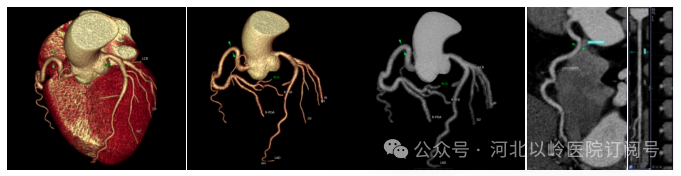

心脏冠状动脉成像

机架0.25s的超高转速,可在单次心动周期内即完成冠脉检查扫描,使得冠状动脉检查成功率接近100%,在冠状动脉血管病变的筛查、冠状动脉支架和搭桥血管评价等方面极具优势。相对于传统CT做冠脉CTA检查,超高端螺旋CT设备在患者有心律过高、心律不齐或房颤等情况下,依旧可以获得清晰的图像,这对于心血管疾病的诊断和治疗具有重要意义。